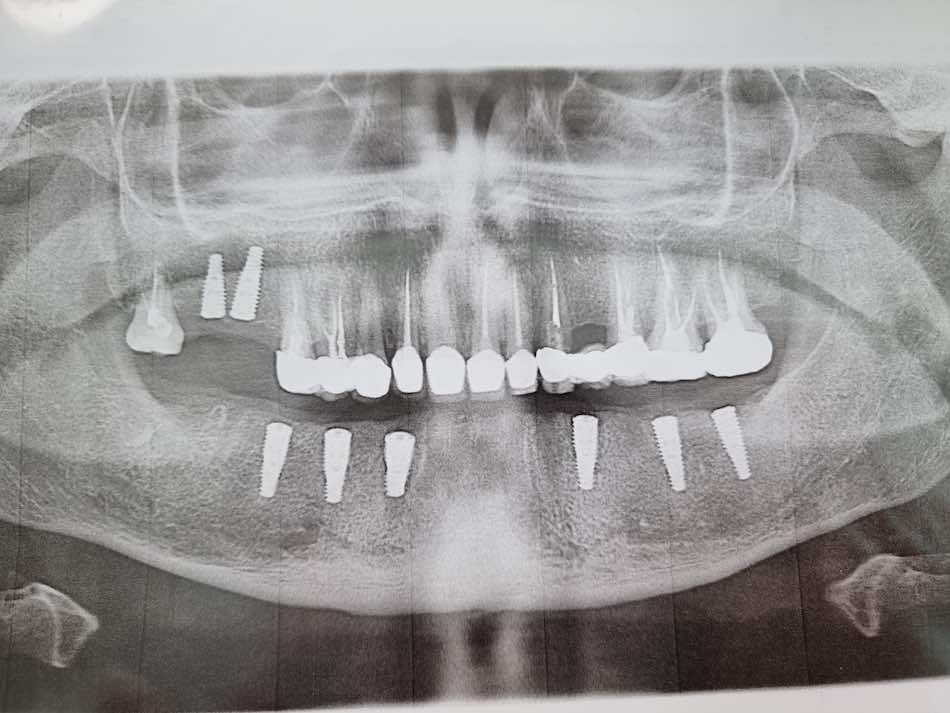

Сканы КТ имплантации зубов, 2026-04-18

Скан КТ, 2026-04-18

Сканы КТ имплантации зубов, 2026-04-18

Скан КТ имплантации зубов, 2026-04-17

Сканы КТ имплантации зубов, 2026-04-18

KT: имплантация зубов DentalKnysh, 2025-01-03, сканы

KT: имплантация зубов DentalKnysh, 2025-01-03, сканы

KT: имплантация зубов DentalKnysh, 2025-01-03, сканы

Фото отчет по имплантации обеих челюстей было установлено 28 циркониевых коронок на 12 имплантах 2024-01-31

КТ имплантации зубов в DentalKnysh (10 имплантов), 2023-11-03

Имплантация зубов (13 шт) и 2 синуслифтинга 2023-10-06

С 2023-09-05 по 2023-09-09 сканы КТ от 6 до 12 имплантов в DentalKnysh (4 фото):

Синуслифтинг и имплантация зубов, 6 имплантов, all-on-6, КТ скан 1, 2023-08-31

Фото отчет Имплантация зубов, 6 имплантов, КТ скан 3, 2023-08-31

Фото отчет Имплантация зубов, 8 имплантов, all-on-4, КТ скан 1, 2023-08-31